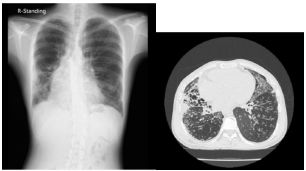

7.CC: cough for one year and back pain